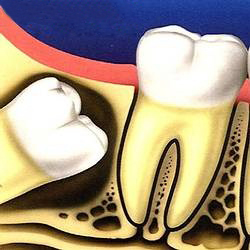

Khi răng khôn gây ra hoặc có xu hướng gây ra tác hại đối với răng, lợi và xương ở xung quanh thì cần nhổ. 1. Sâu răng Do răng khôn

Răng khôn là răng nằm phía trong cùng của hai hàm răng của người trưởng thành. Răng khôn (răng số tám hay răng hàm lớn thứ ba) là răng mọc cuối

Đau đầu, sưng lợi, khó nhai,… là hệ quả do việc mọc răng khôn đem lại. Để giảm bớt những phiền toái này, bạn hãy tham khảo gợi ý dưới đây